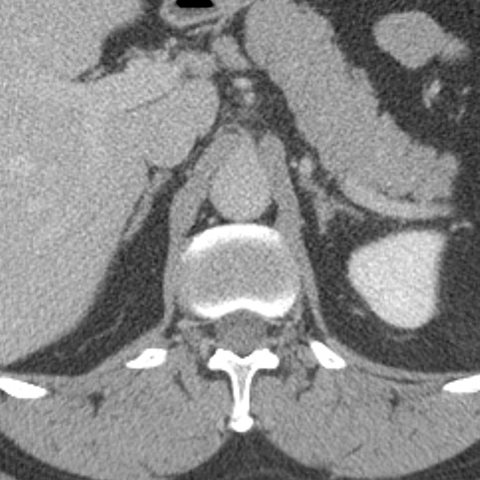

Normal Adrenal glands, CT [1 of 3]